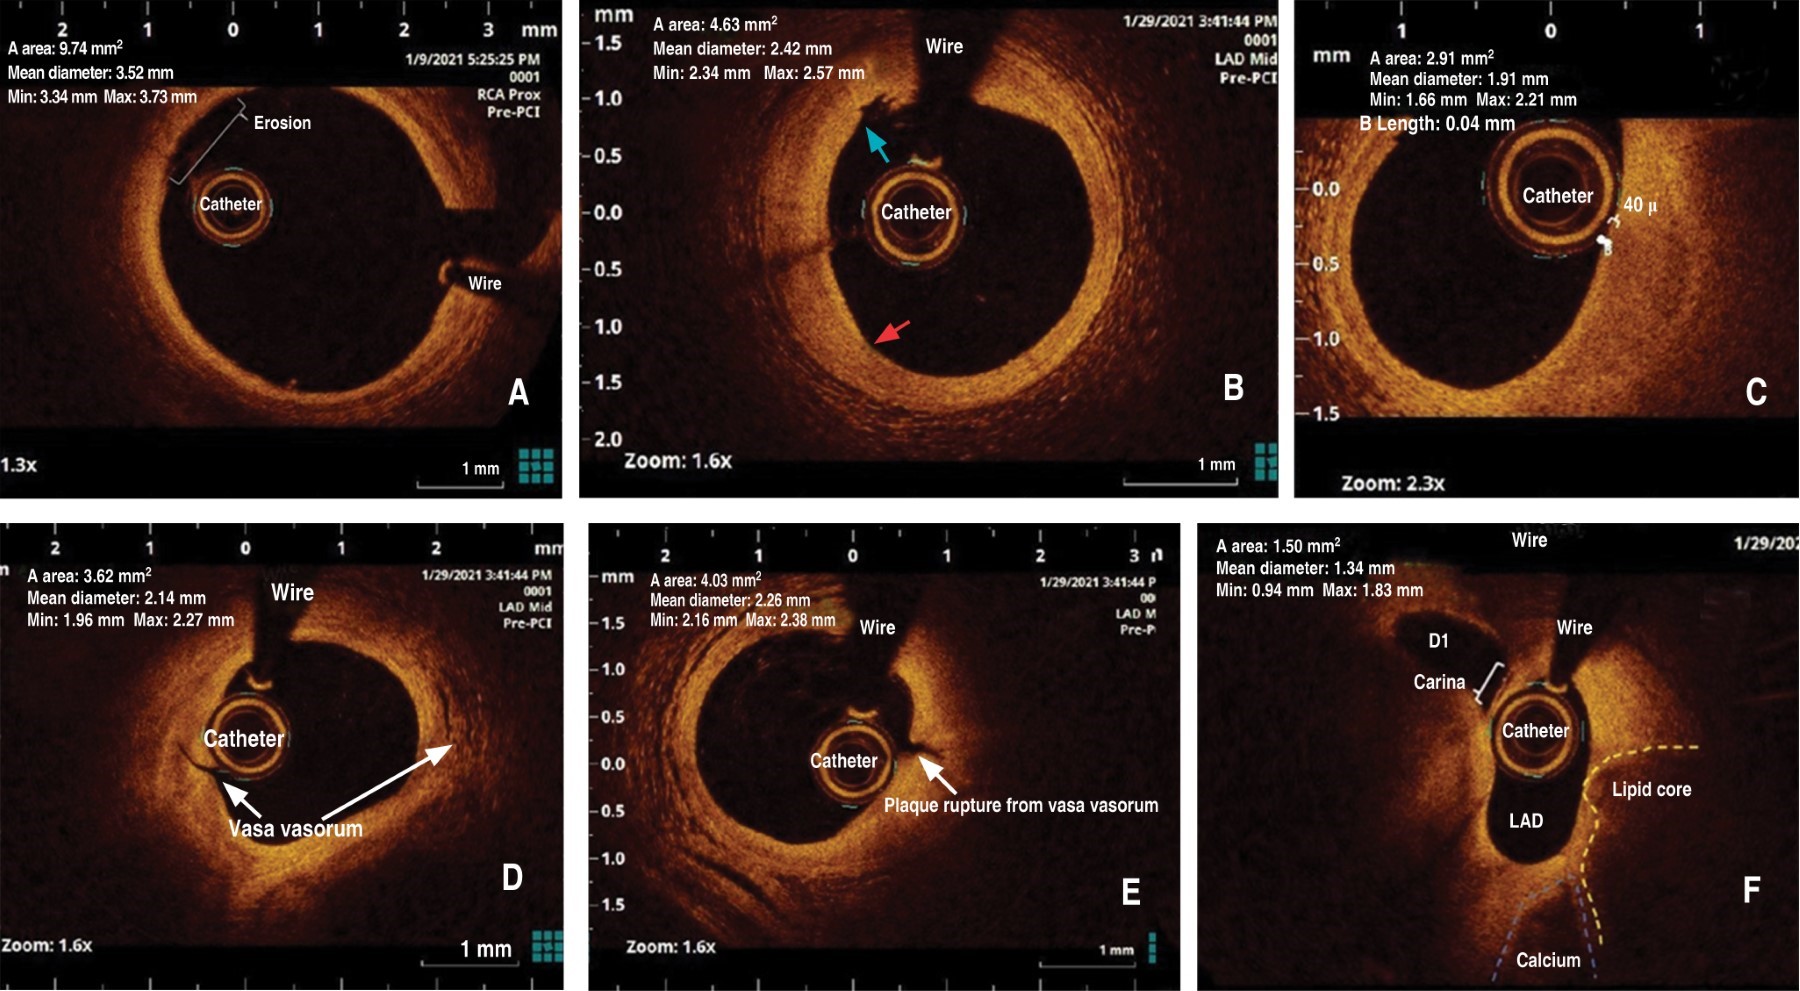

Several diagnostic tools, aimed to visualize the anatomical aspects of the atherosclerotic plaque in vivo, such as the optical coherence tomography (OCT) obtained during cardiac catheterization have been recently developed. This imaging tool can distinguish the coronary arteries' layers with high resolution, well beyond the intravascular ultrasound. The sensitivity and specificity may reach over 90% for detecting fibrous plaque, fibroatheroma, and fibrocalcific plaque. It may detect very small processes such as microthrombi, erosion, ulcers, macrophage aggregates, calcific nodules, lipid core, thin cap, vasa vasora, microdissections, and intra-plaque hemorrhage.19 Some examples of images obtained in our catheterization laboratory show some of the aspects described above (Figure 1).

Figure 1